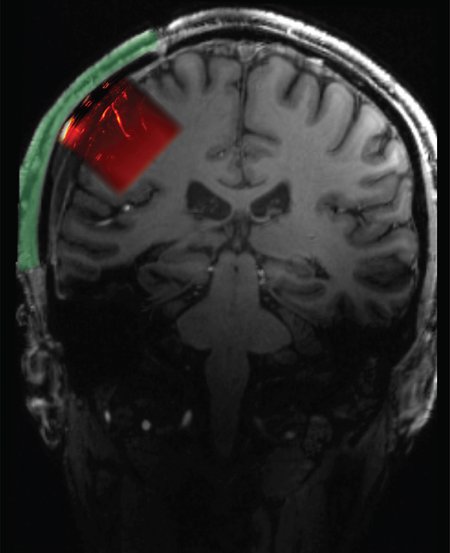

Για να επιτευχθεί αυτό το κατόρθωμα, οι ερευνητές εμφύτευσαν ένα υλικό στο κρανίο του άνδρα που επέτρεπε στα υπερηχητικά κύματα να εισέλθουν στον εγκέφαλό του.

Αφού εισήλθαν μέσα από αυτό το “ακουστικά διαφανές” παράθυρο, αυτά τα κύματα αναπήδησαν στα όρια μεταξύ των ιστών. Μερικά από τα κύματα αυτά επέστρεψαν στη συνέχεια στον υπερηχητικό καθετήρα, ο οποίος συνδέθηκε με έναν σαρωτή. Τα δεδομένα επέτρεψαν στους επιστήμονες να δημιουργήσουν μια εικόνα για το τι συνέβαινε στον εγκέφαλο του άνδρα, παρόμοια με τον τρόπο που οι απεικονιστικές εξετάσεις μπορούν να απεικονίσουν ένα έμβρυο στη μήτρα.

Αντίστοιχα, το ανθρώπινο κρανίο αποτελούσε πάντα ένα εμπόδιο για τα υπερηχητικά κύματα, εμποδίζοντάς τα να εισέλθουν στον εγκέφαλο. Γι’ αυτό, στη νέα μελέτη, ο Liu και οι συνεργάτες του ξεπέρασαν αυτό το εμπόδιο δοκιμάζοντας την προσέγγισή τους σε έναν ασθενή στον οποίο είχε αφαιρεθεί ένα τμήμα του κρανίου του. Αυτό είχε γίνει για να μειωθεί η πίεση στον εγκέφαλό του μετά από σοβαρό τραυματικό τραυματισμό εγκεφάλου (ΤΤΕ).

Συνήθως, στους ασθενείς με ΤΤΕ που υποβάλλονται σε αυτή τη διαδικασία τοποθετείται ένα πλέγμα τιτανίου ή ένα ειδικά κατασκευασμένο εμφύτευμα για να αντικαταστήσει το χαμένο τμήμα του κρανίου τους. Στην περίπτωση αυτή, η ομάδα κατασκεύασε το ακουστικά διαφανές εμφύτευμα. Οι συγγραφείς της μελέτης δήλωσαν ότι στο μέλλον, η νέα τεχνική μπορεί να μην περιορίζεται μόνο σε ασθενείς με ΤΤΕ.